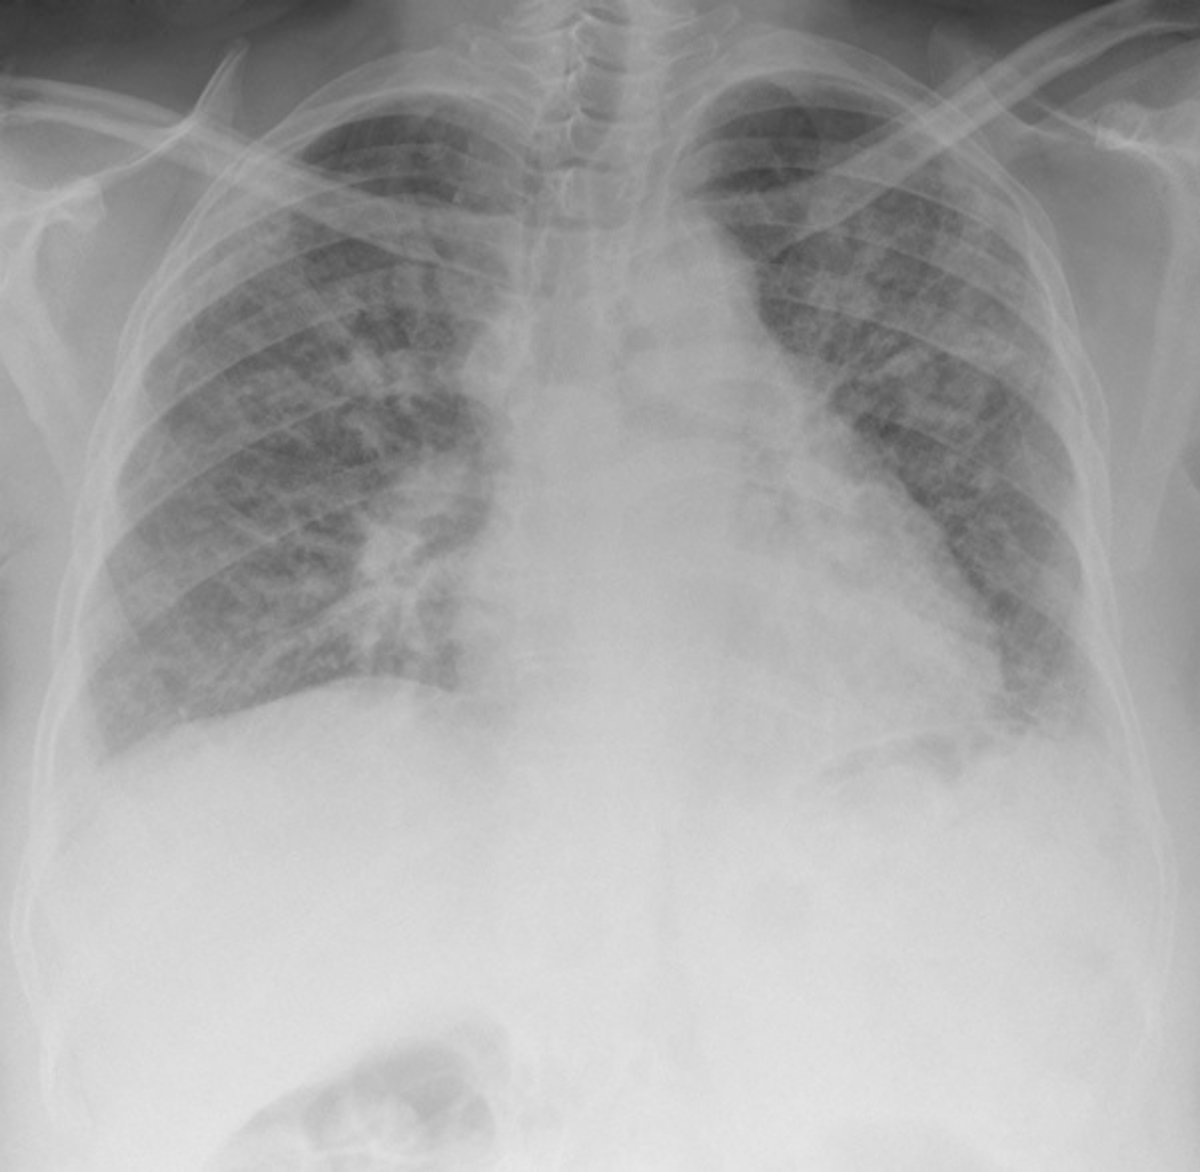

Fibrosis quística

GETTY/WILLSIE - Archivo